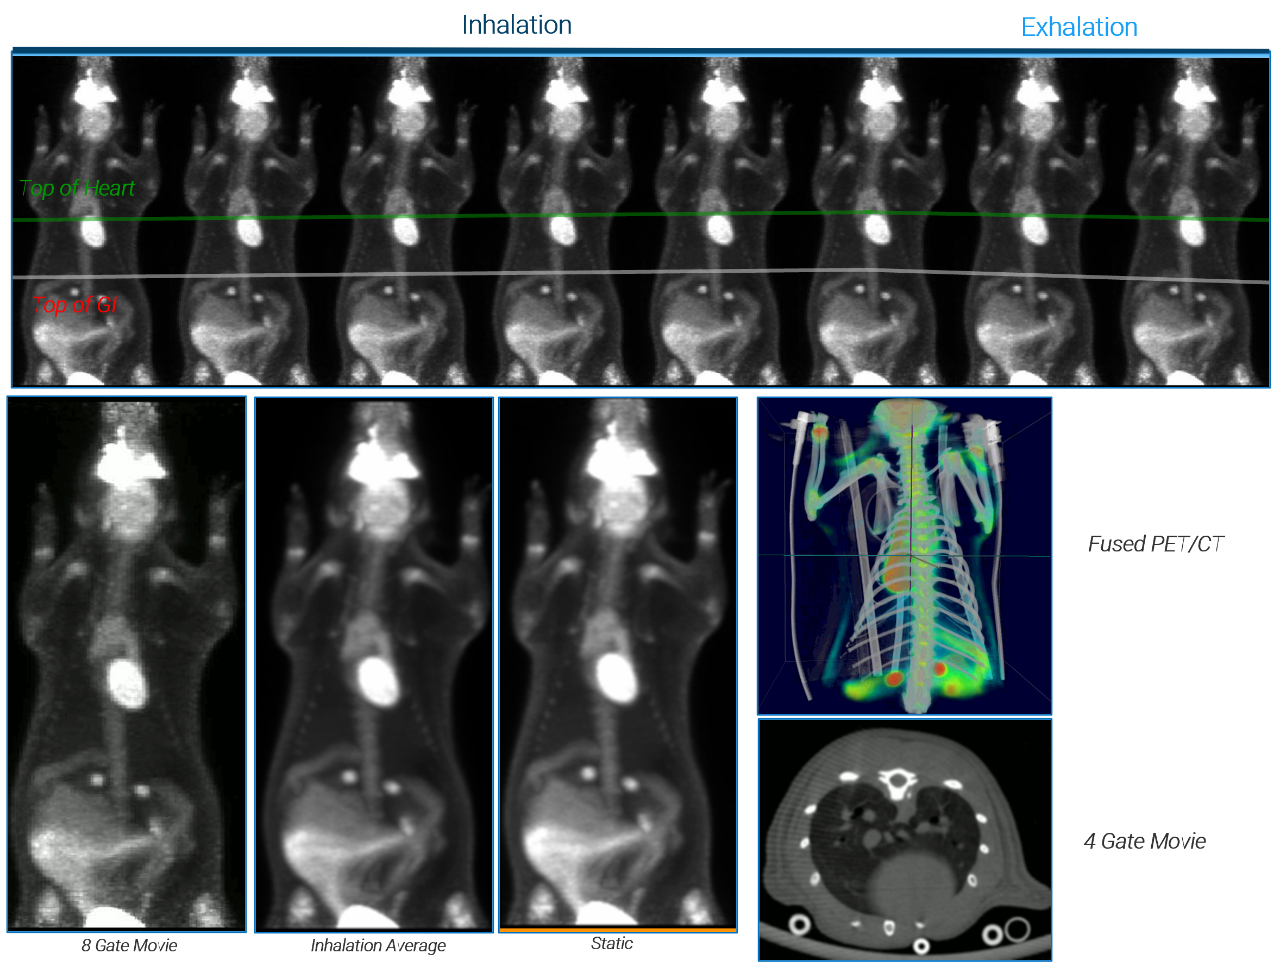

Total Body PET Capabilities

Multi-Animal Dynamic 18FDG-PET/CT in a Mouse Tumor Model

Dynamic PET with low dose injection: 3 MBq 18FDG

PET/CT Si78 in Rat

Abdomen & Thorax